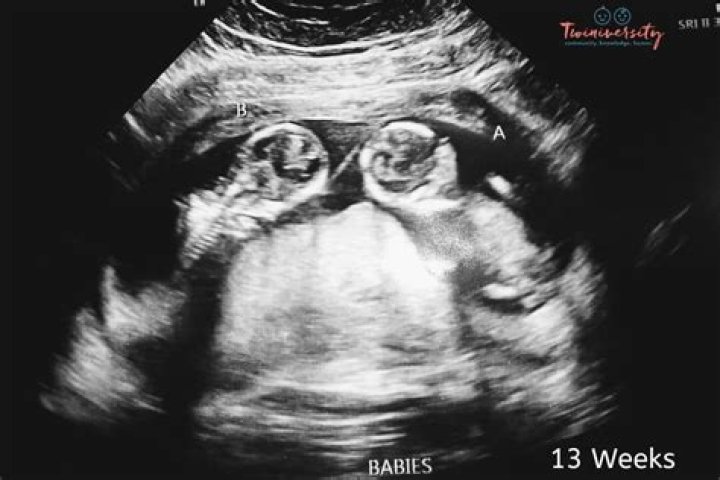

How many ultrasounds do you have during your pregnancy?

Most healthy women receive two ultrasound scans during pregnancy. “The first is, ideally, in the first trimester to confirm the due date, and the second is at 18-22 weeks to confirm normal anatomy and the sex of the baby,” explains Mendiola.